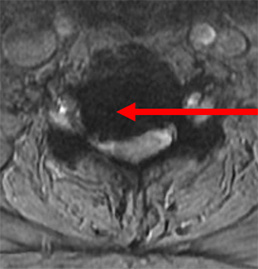

48 year old cook presents with dropping her kitchen tools and feeling clumsy. MRI shows severe spinal cord compression. The spinal cord is bruised as well (arrow). The left image is a side view. The middle view is a cross section of a normal spine. The right shows the spinal cord (arrow) being compressed.

Because of her age and wanting flexibility, we did a laminoplasty. We created more room for her spine and did not do a fusion. It is motion preserving. Left image is a side view MRI showing more space for the spinal cord. The middle picture is a cross section of the same level that showed cord compression now wide open.